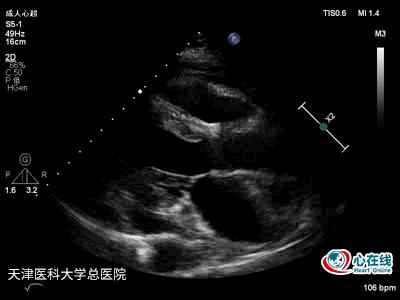

图1. 二维胸骨旁左心室长轴切面示左心房增大,左心室内径正常,室间隔及左心室后壁厚度及运动正常,右心室流出道内径及前壁运动正常,前心包腔舒张末可见2 mm液性暗区,后心包腔舒张末可见13 mm液性暗区。